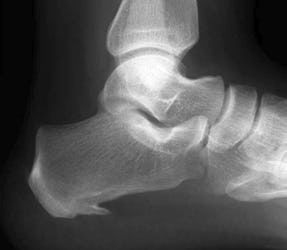

photo Fasciite plantaire

Fasciite plantaire

La fasciite plantaire est également appelée syndrome de l'épine de Lenoir.